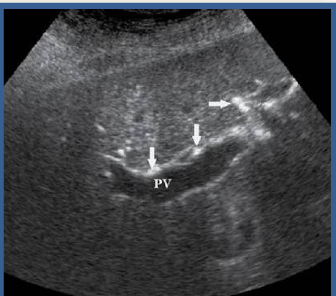

patent TIPS

clotted TIPS